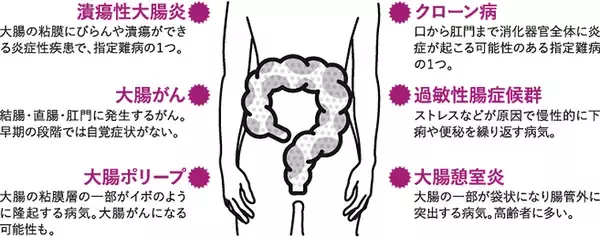

自宅でガマンしながら過ごしていると、知らぬ間に襲いかかってくるストレス。いま、気づかないうちに「大腸劣化」が深刻化しつつあるなか、どう身を守ればいいか――――。新型コロナウイルス感染拡大で、テレワーク...